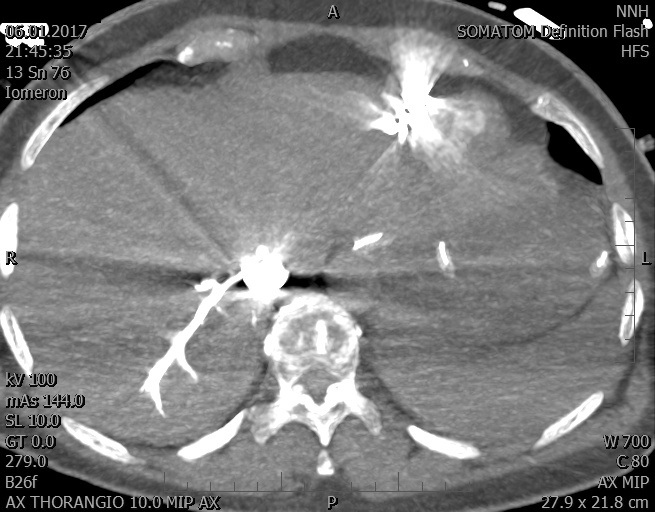

Video 2 - Echokardiograficky byla zjištěna těžká dysfunkce dilatační levé komory s nezvětšenou pravou komorou.Pro nejasnou příčinu zástavy jsme provedli i vyšetření výpočetní tomografií (CT), které vyloučilo plicní embolizaci (série 1 - soubory na konci článku). V den přijetí při přetrvávající oběhové nestabilitě byla nemocná opakovaně defibrilována pro fibrilaci komor se stabilizací rytmu po podání amiodaronu a mesocainu. Dle hemodynamických měření se jednalo o těžký kombinovaný šok. Vstupní laboratorní vyšetření bylo bez větších pozoruhodností. Posléze jsme doplnili anamnézu od příbuzných a zjistili, že pacientka užila do dvou hodin před srdeční zástavou první tabletu amoxicilinu na lehký respirační infekt. Při nevýtěžnosti vstupních vyšetření a nových anamnestických informacích jsme doplnili 14 hodin po kolapsu vyšetření koncentrace tryptázy v séru, která byla extrémně zvýšena (tabulka 2), což nás vedlo k podezření na anafylaxi.